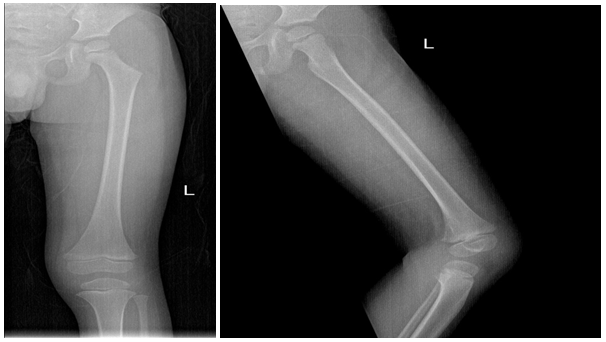

As part of primary survey patient’s chest and pelvis X-rays done at trauma bay shows no abnormality. AP and lateral X-rays of left femur showing hip and knee joints were reviewed by different ranked orthopaedics surgeons with agreement of normal x-ray impression (Figure 1 & 2). The following visits for the same complain has different x-rays with same impression of normal x-ray (Figure 3). Except for the one at last visit with the clinical evidence of deformity, patient has diaphysial femur fracture (Figure 4 ).

Figure 3 Different x-rays with same impression of normal x-ray.

Figure 4 X ray showing diaphysial femur fracture.